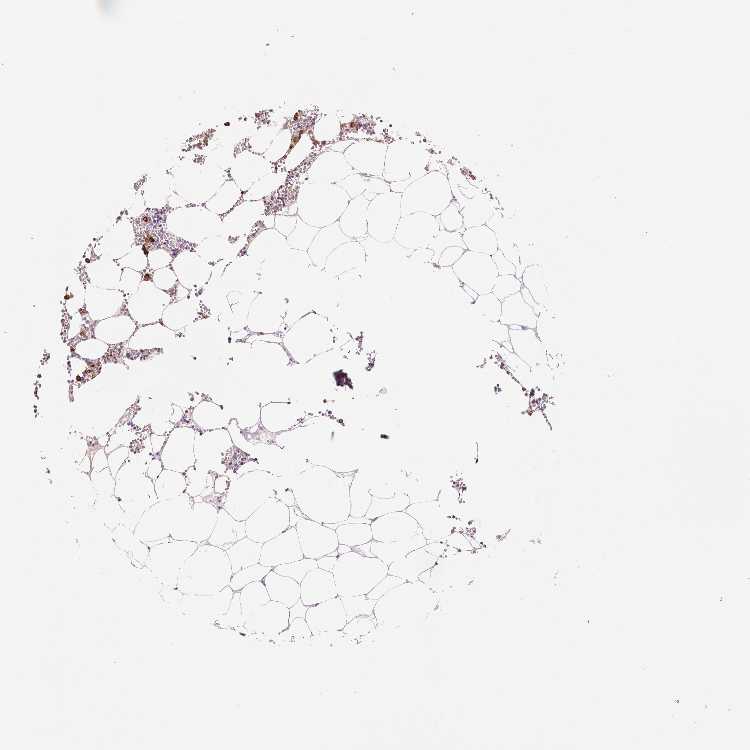

BONE MARROW - Antibody stainingi

Antibody staining in the annotated cell types in the current human tissue is reported as not detected, low, medium, or high, based on conventional immunohistochemistry profiling in selected tissues. This score is based on the combination of the staining intensity and fraction of stained cells.

Each image is clickable and will lead to virtual microscopy that enables deeper exploration of all samples and also displays staining intensity scores, fraction scores and subcellular localization as well as patient and tissue information for each sample.

Antibody HPA021147Antibody HPA061464Antibody CAB000059Antibody CAB080352Antibody CAB080353Antibody CAB080354

Hematopoietic cells LowHighMediumHighHighHigh